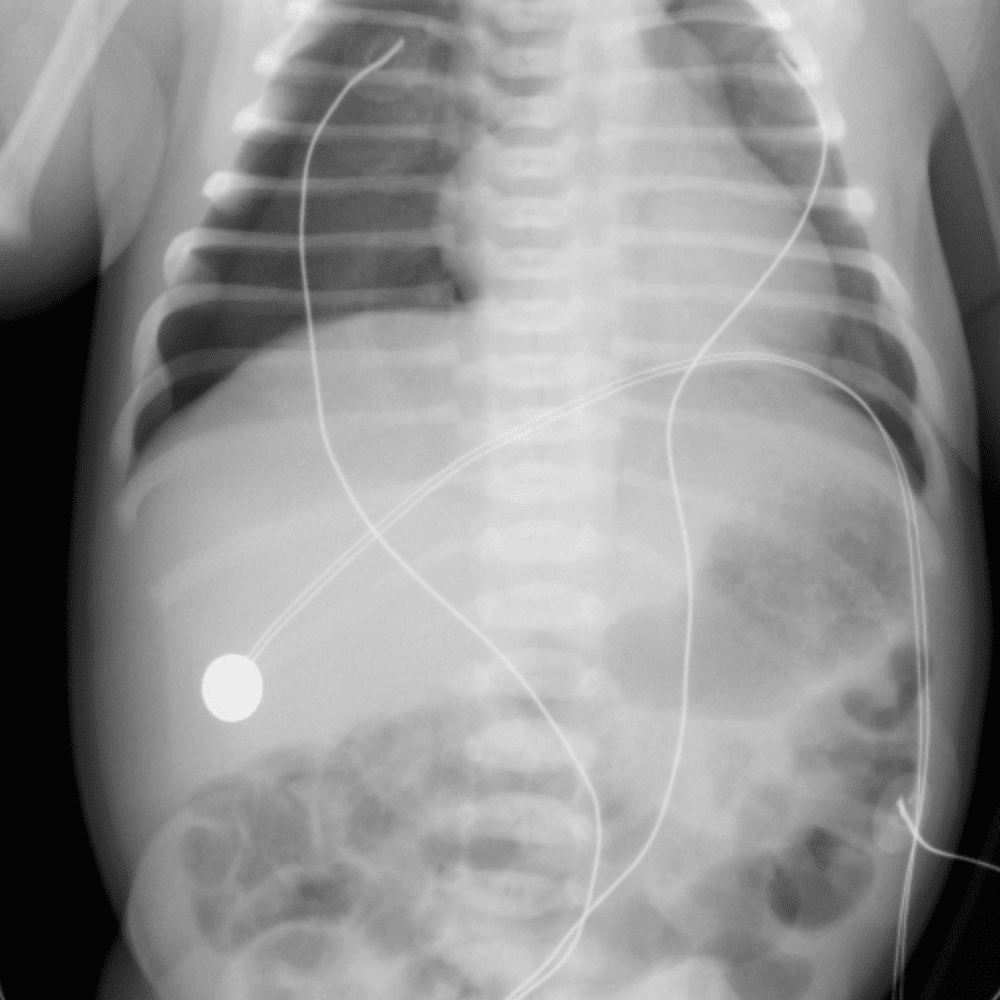

Peds Chest

Practice

Simulates call by including subtle or difficult cases and some normals.

50 cases